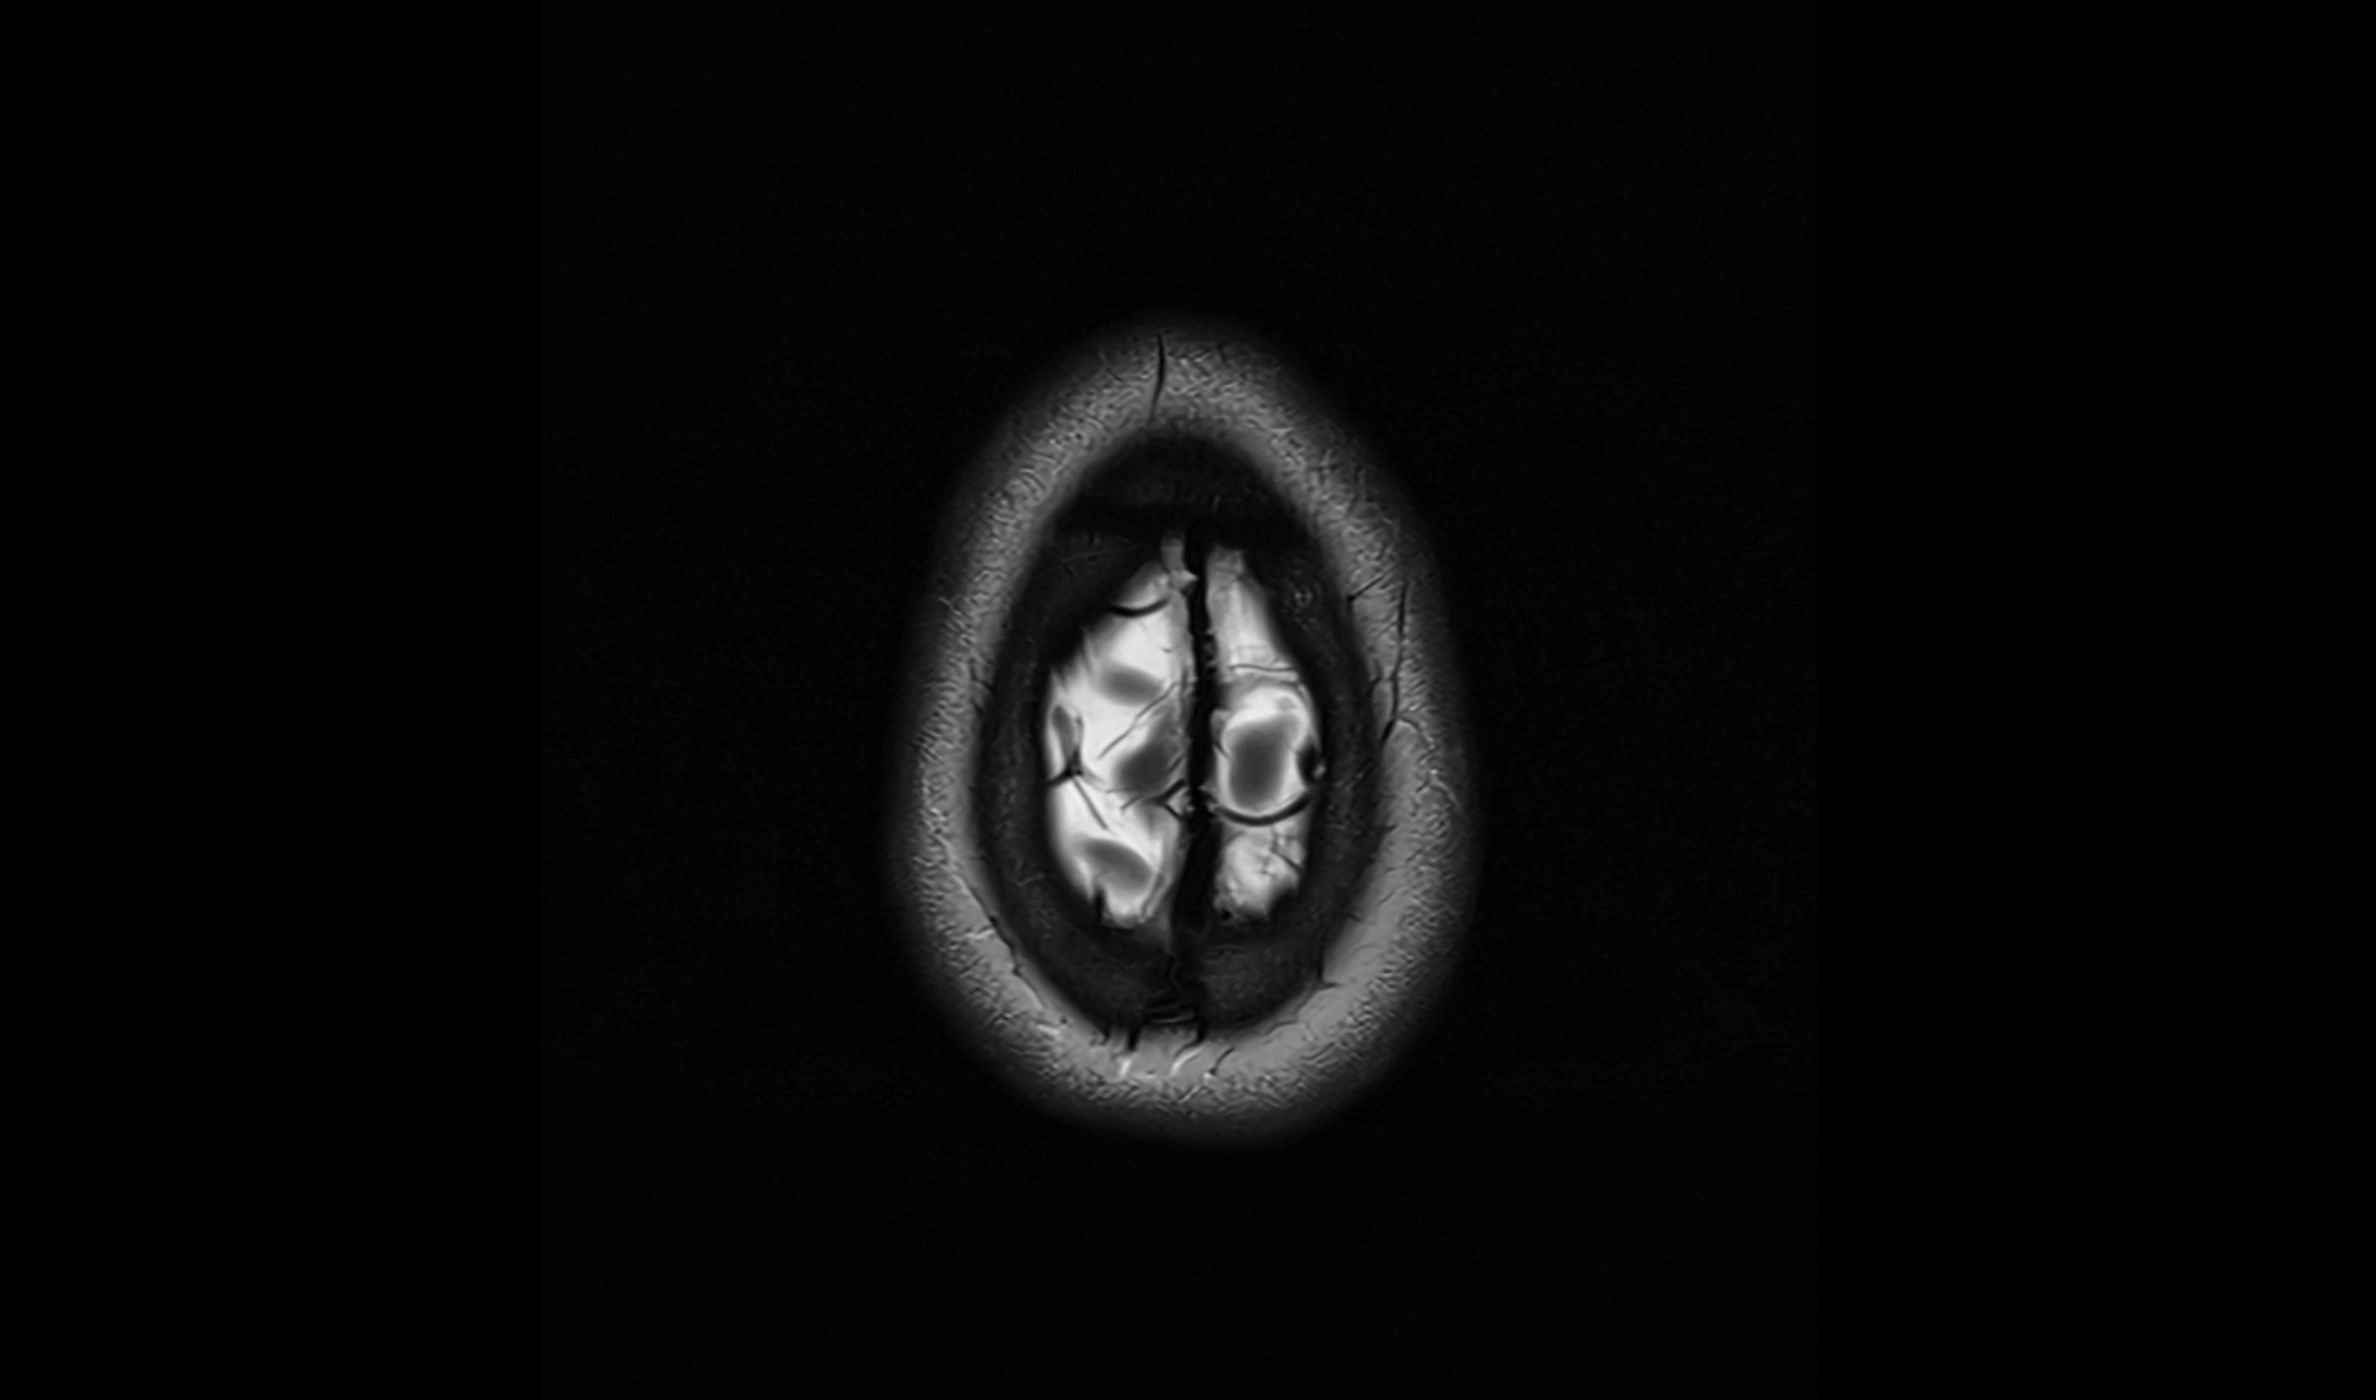

CT image

image